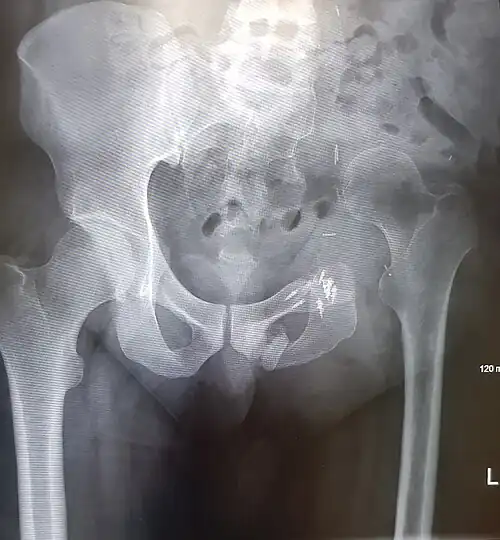

An x-ray of the same pelvis taken eighteen months after surgery highlighting the femur migration to its final resting place.